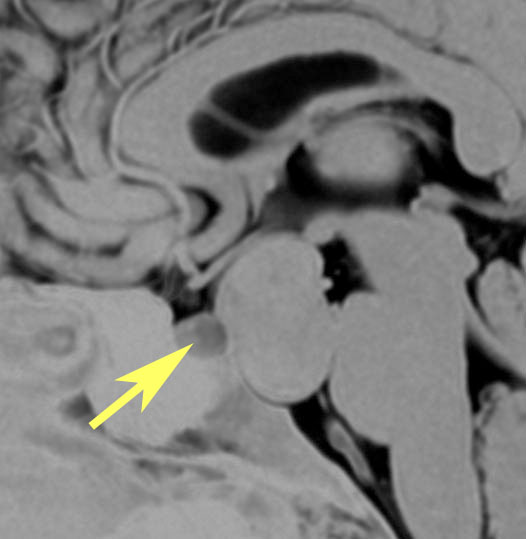

肉芽腫になってしまった第3脳室コロイドのう胞

CTでは壁が厚く高密度,MRI T2強調画像では低信号,T1強調画像では高信号です。内部に血液を含んでいるようなのう胞に見えます。のう胞の壁は非常に厚く硬いものが予想されます。閉塞性水頭症になっています。

若い男性ですが,内視鏡手術では摘出できない壁がガチガチのものでした。モンロー孔が広いので経脳梁到達法 transcallsal approachで手術しました。右前頭部から入ろうとしましたが,架橋静脈のために入れず,左前頭葉を除けて,透明中隔の正中に達しました。ところが,左の脳弓が菲薄化して広がり腫瘍の上面にみえましたから,左のモンロー孔からは摘出できませんでした。しかたがないので,右のモンロー孔から腫瘍を摘出しています。腫瘍の周囲には第3脳室脈絡叢が広範囲に癒着していました。のう胞内容は暗褐色の古い血腫でした。のう胞の壁は硬く厚い結合織で肉芽腫のような肉眼所見でした。左右の脳弓にも癒着し,内大脳静脈にも癒着していたので,その部分には皮膜を残しました。

術後のMRIです。幸い,記憶障害などの脳弓症状はでませんでしたが,かなりリスクの高い手術でした。

のう胞壁の組織像は大部分が線維性に肥厚した結合織膜でした。裂け目のように見えるのはコレステロール choresterol crystalが抜けた部分です。その間に異物巨細胞(黄色の矢印)が多数見られます。のう胞内容が古い血腫でしたから, ヘモジデリンを貪食したマクロファージ (CD68+)が見られ慢性炎症所見です。病理診断としては,コレステロール肉芽腫 chorelsterol granulomaとなります。免疫組織染色でCam5.2陽性の細胞があり扁平ないし立方上皮を形成していました。病理診断では,第3脳室コロイドのう胞が変性消褪して瘢痕化した病変と結論付けられました。